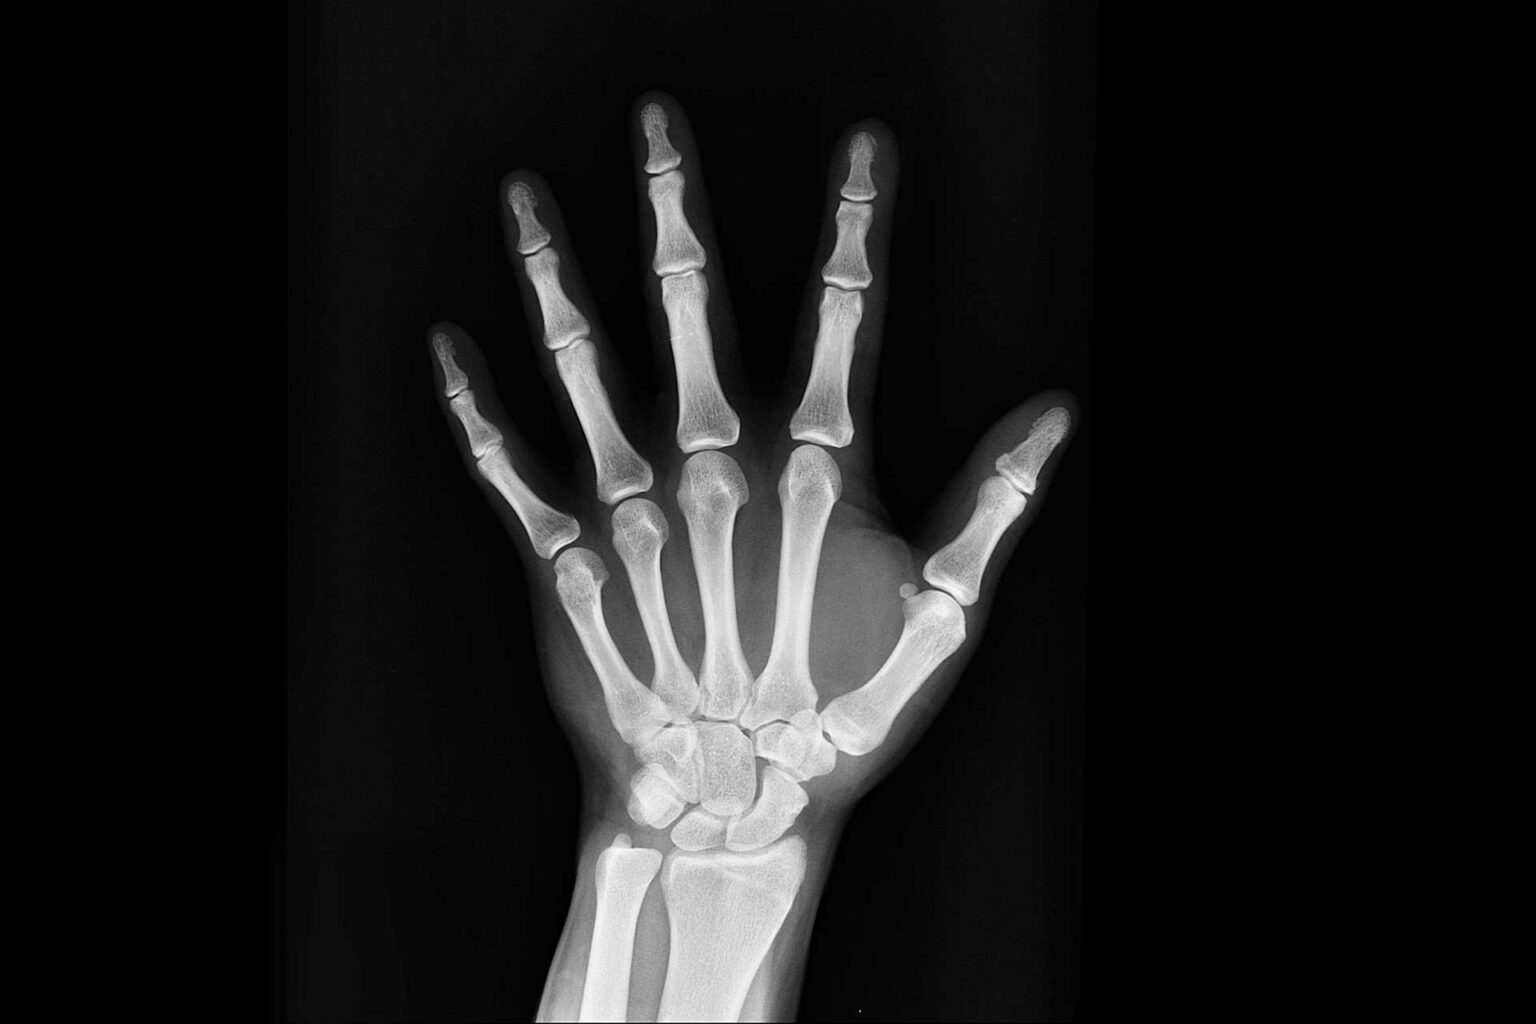

Die Knochenheilung, auch Bruchheilung (und Frakturheilung) genannt, nach einem Knochenbruch kann je nach Art des Bruchs (Fraktur) und der medizinischen Versorgung auf zwei Wegen erfolgen: als primäre und als sekundäre Knochenheilung.

Eine primäre Knochenheilung kann nur dann erfolgen, wenn die Bruchenden möglichst frühzeitig nach der Fraktur eng adaptiert werden und sie nicht gegeneinander beweglich sind. Dies ist in der Regel nur bei chirurgischer Versorgung mittels Osteosynthese der Fall.

Bei der primären Knochenheilung bildet sich kein äußerer Kallus. Die Knochenbälkchen (Substantia spongiosa) wachsen durch Anlagerung von neugebildetem Knochengewebe zusammen. Dieses Knochengewebe wird durch Aktivierung der Osteoblasten der inneren Knochenhaut (Endost) gebildet. Im Bereich der Markhöhle der Röhrenknochen bildet sich meist ein innerer Knochenkallus aus Knochenbälkchen. Die Osteone der kompakten Knochensubstanz (Substantia compacta) der beiden Bruchenden können bei sehr guter Adaption (Spalt < 300 µm) von beiden Bruchenden aufeinander zuwachsen und wieder fusionieren. Das neuentstandene Knochengewebe hat zunächst eine geringere mechanische Belastbarkeit. Es wird dann etwa ab der 8. Woche durch Osteoklasten wieder abgebaut und durch entsprechend den Druck- und Zugbelastungslinien des Knochens (Trajektorien) ausgerichtetes Knochengewebe ersetzt (sogenanntes remodeling).

Eine sekundäre Knochenheilung tritt bei weniger guter Adaptation und Fixation der Bruchenden sowie bei größeren Knochendefekten – wie nach einer Trümmerfraktur – auf.

Zunächst tritt aus der Bruchfläche Blut aus und es bildet sich ein Bluterguss (Hämatom). Dies führt zu einer Aktivierung der Entzündungskaskade und Entzündungszellen setzen Zytokine wie Interleukin-1 und Interleukin-6 frei. Das Blut gerinnt, wird durch Granulationsgewebe ersetzt und es bildet sich zunächst eine bindegewebige Narbe. Diese Prozesse bilden zunächst eine elastische Verbindung der Bruchenden und schränken deren Beweglichkeit ein. Durch eingewanderte Knorpelbildner (Chondroblasten) kommt es zur Bildung von Faserknorpel, der allmählich durch aktivierte Osteoblasten verknöchert. Die so entstandene Manschette ist deutlich dicker als der übrige Knochen und wird als «Kallus» bezeichnet. Die mechanische Stabilität des Kallus ist jedoch deutlich geringer als die von intaktem Knochengewebe. Auch bei der sekundären Knochenheilung setzt nun ein Knochenumbau (remodeling) ein, und der Kallus wird nach und nach abgebaut und durch entsprechend den Trajektorien ausgerichtetes Knochengewebe ersetzt. Je nach Ausmaß der Fraktur kann die vollständige Knochenausheilung zwischen sechs und zwölf Monaten dauern.